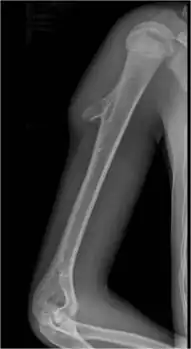

| Osteochondroma[2] | ![]() | |

Chondrogenic tumors are the most common type of bone tumor that arise from bone itself.[1] Cancerous chondrogenic tumors represent around 25% of all cancerous bone tumors.[1] Osteochondroma and enchondroma are the most common non-cancerous types, and conventional chondrosarcoma is the most common cancerous type.[1]

Of all chondrogenic tumors, 28.5% are osteochondroma, 29.1% enchondroma, 21.7% conventional chondrosarcoma grade I-III, less than 5% are subungual exostosis and bizarre parosteal osteochondromatous proliferation combined, and the least common is mesenchymal chondrosarcoma at less than 1%, as reported by the WHO in 2020.[1]